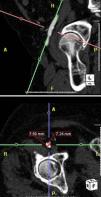

Material e métodosAnalisamos retrospetivamente 145 doentes consecutivos referenciados ao nosso centro para IVAP, desde março de 2007 até outubro de 2011. Todos os doentes foram avaliados por ecocardiograma transesofágico (ETE) e por tomografia computadorizada multidetetores (TCMD). Para a avaliação do diâmetro do anel aórtico foi privilegiada a dimensão obtida por ETE, sendo a medição efetuada no plano do eixo longo do ventrículo esquerdo a 120-140° (Figura 1). O diâmetro luminal mínimo das artérias iliofemorais foi determinado por TCMD em toda a extensão proximal à cabeça do fémur, tendo sido selecionada a dimensão da artéria com anatomia mais favorável (Figura 2). A proporção de doentes anatomicamente adequados para os diferentes dispositivos e abordagens foi determinada segundo os respetivos requisitos anatómicos (Figura 3).